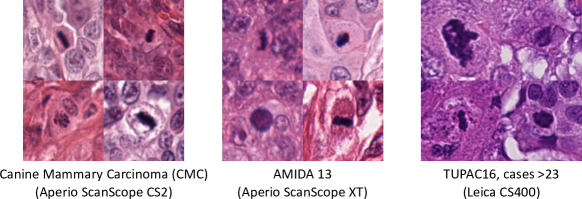

To investigate this, let us have a brief look at the TUPAC16 [10] dataset: According to Veta et al., the dataset was acquired using two scanners of different types at three clinical environments. The first 23 cases, previously released as the MICCAI AMIDA-13 dataset, were acquired using the Aperio ScanScope XT, while the remaining 84 cases were acquired using the Leica CS400 scanner. Both scanners have very different color representation (see Figure 5), and thus cause a severe domain shift, that shall, however, not be the scope of this work, as we only wanted to investigate the general transferability of models trained on canine tissue. The images used for the canine specimens (scanned with Aperio ScanScope CS2) seem to have similar color representation as compared to human images scanned with the Aperio ScanScope XT.